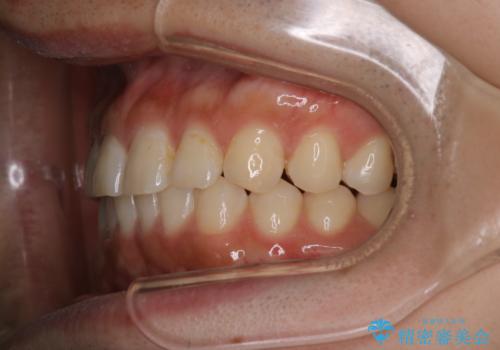

【インビザライン】正中離開を治したい

再矯正ということでがたつきはなくきれいに並んでいましたが、上下のアーチ(歯列弓)の大きさのバランスが悪く、結果的に後戻りの原因になってしまっていました。今回は下のアーチを小さくするためにIPRを行い、かみ合わせのバランスを治しながら前歯の隙間を閉じました。